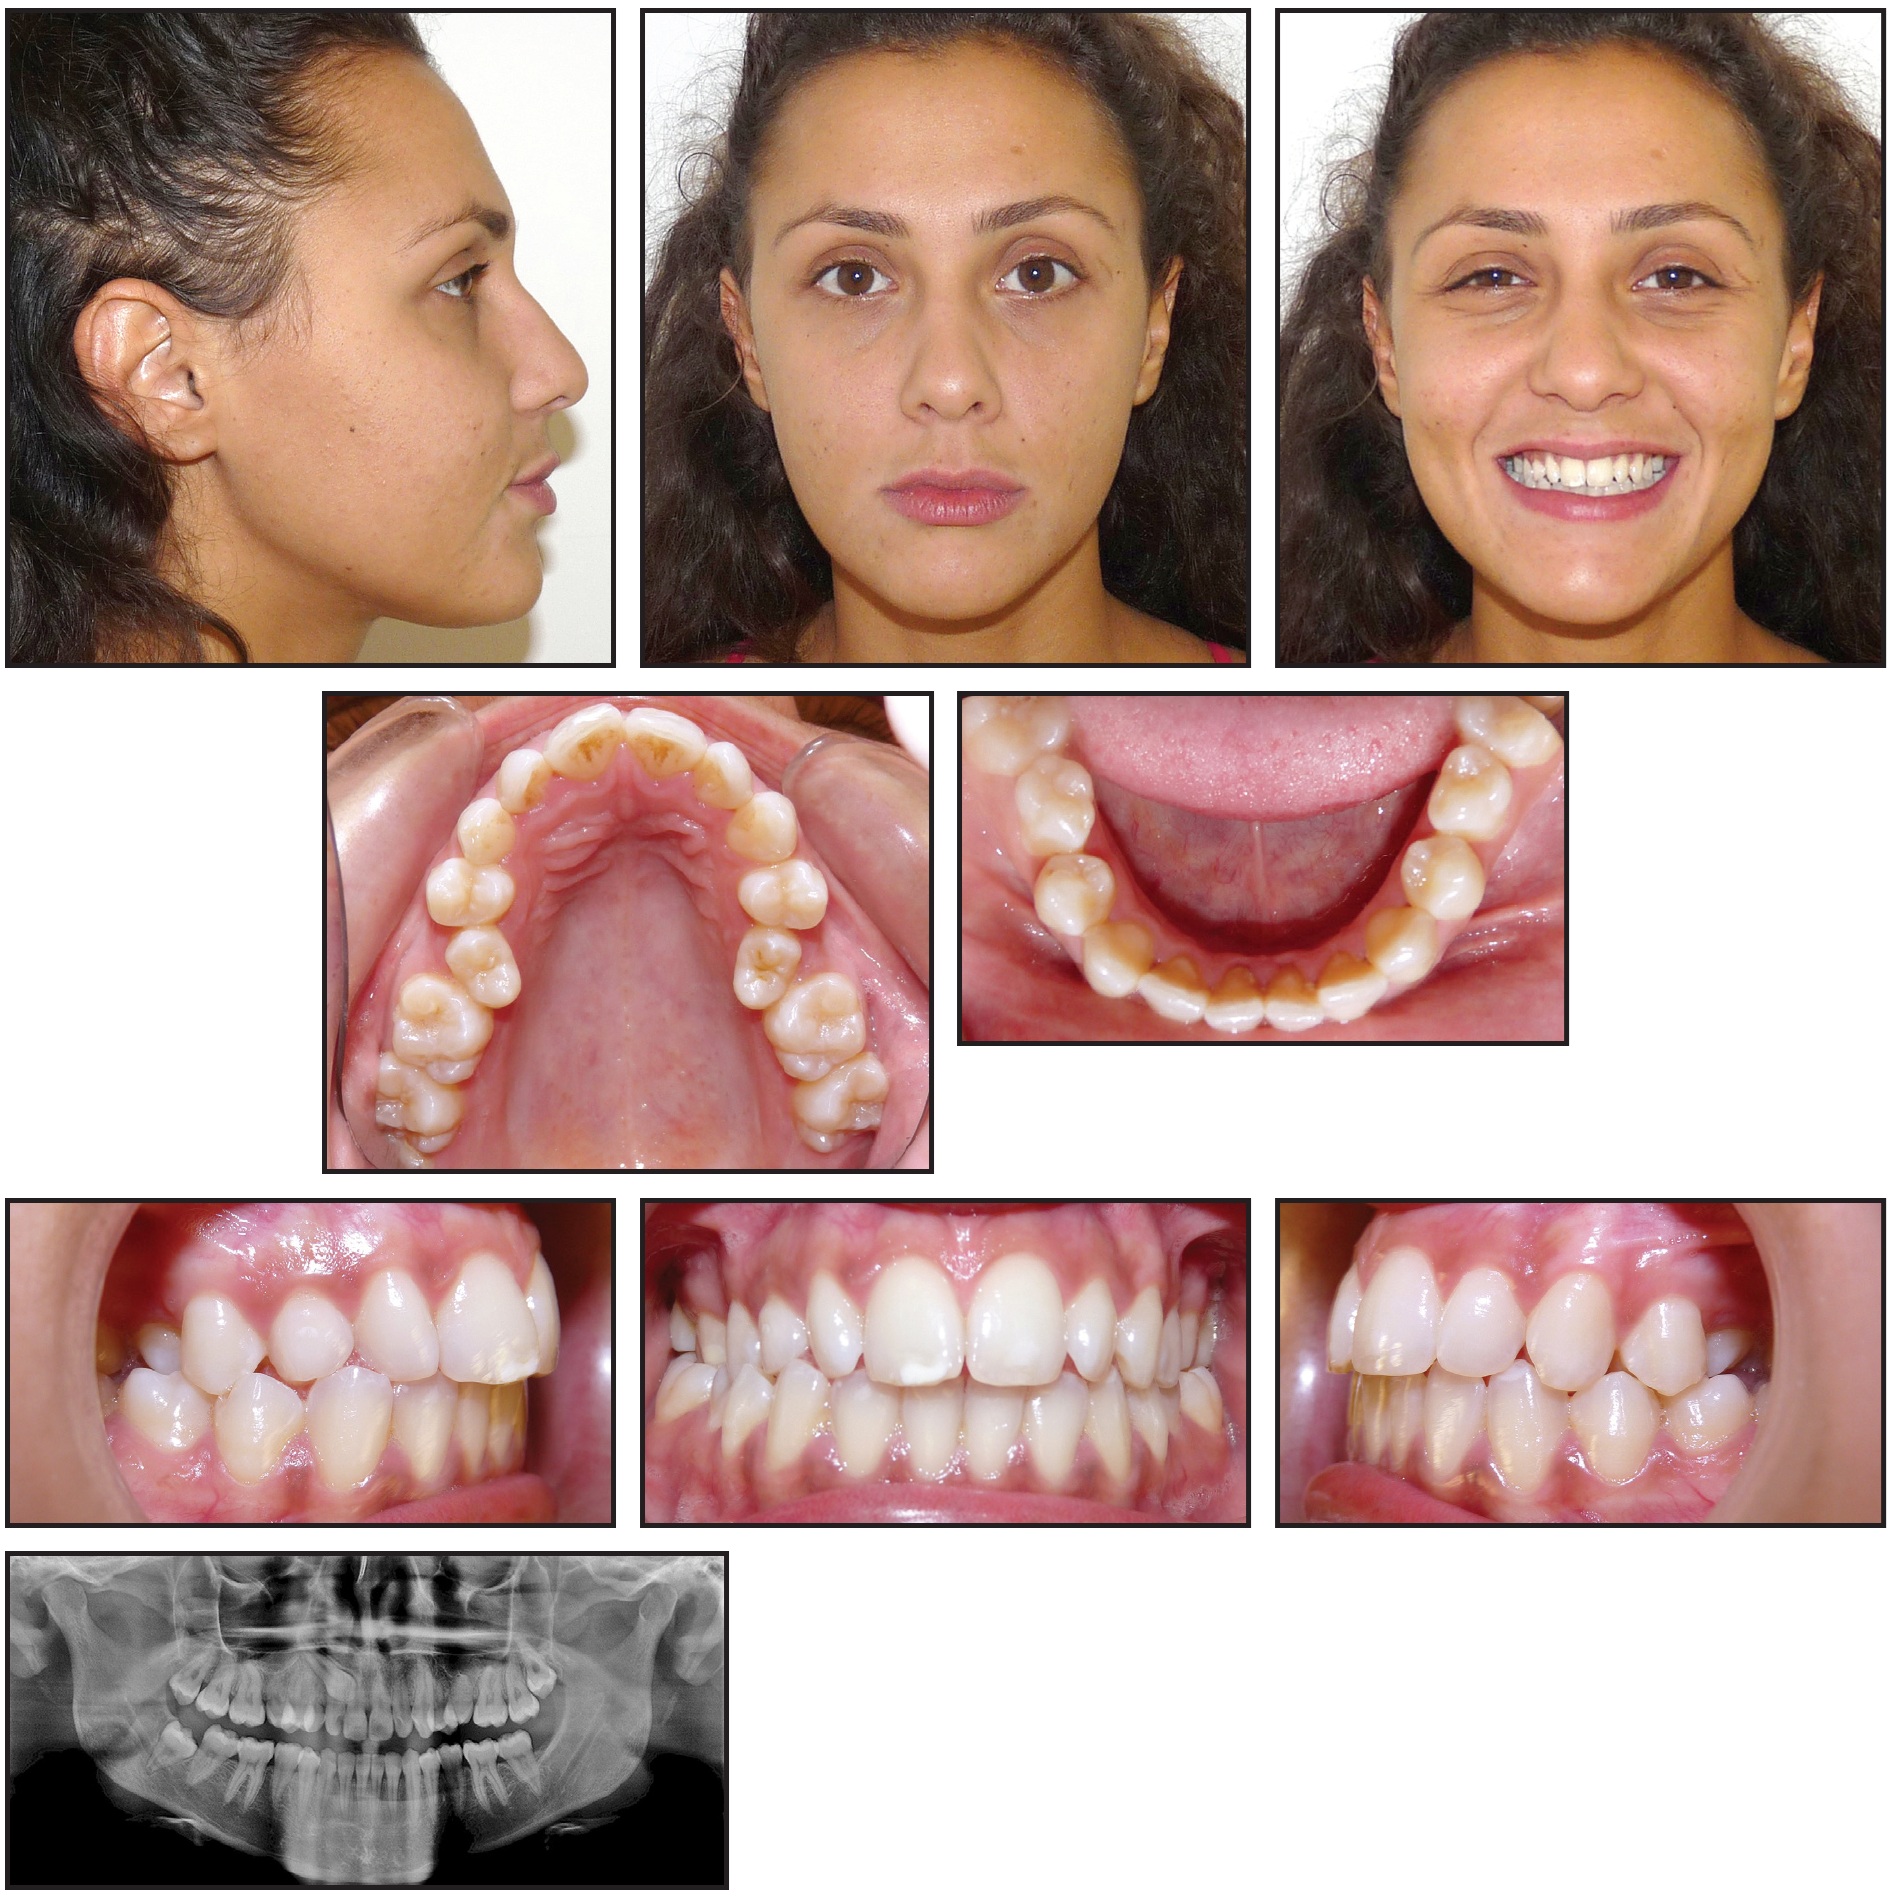

A 19-year-old female presented with the chief complaint of irregular anterior teeth (Fig. 7). The patient had a balanced, well-proportioned soft-tissue profile. The smile arc was non-consonant, with more gingival display on the right posterior side than on the left. The upper right deciduous canine was retained, and the upper second premolars were palatally displaced on both sides. The maxillary arch was constricted and V-shaped; a bilateral posterior lingual crossbite and excessive overjet were noted.

Fig. 7 Case 2. 19-year-old female patient with impacted upper right canine, constricted maxillary arch with bilateral posterior crossbite, and excessive overjet before treatment.

The panoramic radiograph revealed an impacted upper right canine overlapping the roots of the lateral and central incisors.

The treatment objectives were to alleviate the crowding, bring the upper right canine and both upper premolars into the arch, expand the maxillary arch to correct the crossbite, and achieve proper overjet and overbite. Clear aligners would be used, with fixed appliances as auxiliaries.

The treatment plan was divided into two stages (see box). The first, involving arch expansion and space preparation for the canine, would require 44 sets of aligners, changed weekly. In the second stage, which would involve 32 sets of aligners changed every two weeks, the canine would be exposed, and traction would be performed.

The first set of aligners was designed to expand the maxillary arch and prepare space for the upper premolars with sequential molar distalization (Fig. 8). Class II elastics (3⁄16", 4.5oz) were worn from the first premolars to the lower molars to prevent labial movement of the premolars. Next, the premolars were derotated and moved buccally into the arch. Using the contralateral canine’s mesiodistal width as a guide, about 7.5mm of space was prepared for the impacted canine.

Fig. 8 Case 2. ClinCheck plan of first treatment stage, involving expansion of maxillary arch and preparation of space for impacted canine.

After two months, the canine was surgically exposed. A button was bonded to the labial side of the upper right first molar, and elastic thread was used to apply a distobuccal force vector, with the primary objective of moving the canine away from the incisor roots.

After the first stage of treatment, the canine was partially visible and had moved buccally into the arch. Because 30° of derotation would be required for alignment, in addition to extrusion and buccal root-torquing movements, a lingual fixed appliance would be used as an auxiliary; the ClinCheck* plan was modified accordingly (Fig. 9). Lingual .022" Victory** lower-incisor twin brackets were bonded from the upper right central incisor to the second premolar, and an .016" nickel titanium lingual archwire was engaged to correct the rotation. At the same time, clear aligners were used to extrude the upper right canine, with elastics (3⁄16", 3.5oz) worn from the canine hook to cutouts on the labial sides of the canine and first premolar.

Fig. 9 Case 2. A. ClinCheck plan of first refinement stage, showing modifications to account for use of sectional fixed appliance on lingual side of upper right segment. B. Fixed lingual appliance used as auxiliary during first refinement stage.

Four months later, buccal root torque was applied to the canine with an .016" × .022" rectangular TMA*** lingual archwire. During the detailing phase, the fixed lingual appliance was removed, and treatment continued with 12 sets of clear aligners, changed weekly. To reduce the visibility of the attachments, they were placed on the lingual sides of all upper anterior teeth except the right canine.

After 30 months of active treatment, the maxillary and mandibular arches were well aligned, the posterior crossbite was corrected, the overjet and overbite were within normal ranges, and bilateral Class I canine and molar relationships were obtained (Fig. 10). At the end of treatment, a gingivectomy of the canine was performed to align its soft-tissue contours with those of the adjacent teeth.

Fig. 10 Case 2. Patient after 30 months of treatment, showing alignment of impacted upper right canine, correction of posterior crossbite, and normalization of overjet and overbite.